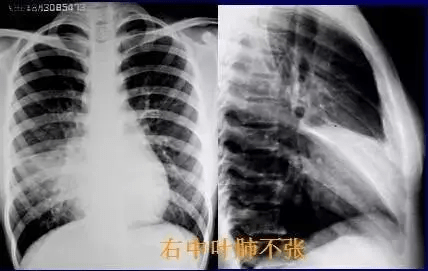

?0? 胸腔莫名“淹水” 憋坏爹爹的肺,医生变“肺”为宝成功治水(通讯员 张全录)胸腔莫名积水,长期“清波荡漾”,处在胸腔内的肺,伸缩空间被压缩大半,72岁患者林师傅(化姓)憋闷多年,多方就医未果。昨天,在武汉市肺科医院,医生巧用“移花接木”术,让肺客串“创可贴”,成功堵住了位于胸壁上的大片挂壁“泉眼”。林师傅感叹,憋闷多年,幸福一下来...